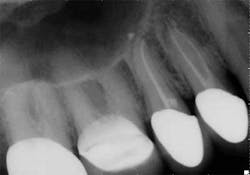

Mandibular premolars

Mandibular premolars can be very difficult to treat and are associated with a high rate of post-treatment disease that is most likely due to anatomic variability. (11) This anatomical variability in mandibular premolars is similar to that of maxillary premolars and is a possible reason why root canal treatment may fail in premolar teeth in general. Similar to maxillary premolars, the clinical crowns taper to a thin root at the CEJ, resulting in very little or no margin for error when accessing the pulp chamber. It is not uncommon to have more than one canal in these teeth. Several studies indicate a second canal is present in more than 25% of mandibular first premolars. (12,15)Often when two canals are present, the second canal is displaced to the lingual and can be very difficult to locate. (Figure 5) Many mandibular first premolars have significant lingual inclination of the root, making the second canal almost impossible to locate because the lingual canal often branches off the main canal at or near a 90-degreeangle. If a single canal is present, it tends to be broad in the buccal-lingual direction, and this makes it difficult to remove biofilm from all root surfaces. Mandibular second premolars also have a high degree of anatomic variability, but not to the same degree as mandibular first premolars. The reported incidence of multiple canals in mandibular second premolars ranges from 1.2% to 29%. (12,18)As with first premolars, many mandibular second premolars have some lingual inclination of the root and a broad buccal-lingual canal dimension results in difficulty contacting all surfaces of the canal with any instrumentation technique.

with conventional radiography, and this branching could be better

visualized with CBCT.